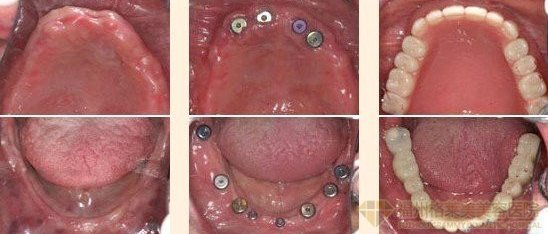

种植牙齿指的是一种以植入骨组织内的下部结构为基础来支持、固位上部牙修复体的缺牙修复方式。将与人体骨质兼容性高的纯钛金属经过精密的设计,制造成类似牙根的圆柱体或其他形状,以外科小手术的方式植入缺牙区的牙槽骨内,再在人工牙根上制作烤瓷牙冠。

由此可见能否做种植牙与牙槽骨是有一定关系的。据广州越秀圣贝口腔门诊部口腔介绍,种植牙与牙槽骨有极大关系。如果牙槽骨不足,人工牙根与牙槽骨就不能很好的结合,有时候甚至不能结合,种植后就会容易出现牙齿松动、脱落等情况。那是不是牙槽骨萎缩就不能做种植牙呢?当然不是,牙槽骨不足可以通过植骨的方式增加骨量,之后就可以进行种植牙了。牙槽骨萎缩怎么办?

广州越秀圣贝口腔门诊部口腔采用亲骨种植牙,骨种植牙就是根据亚洲人骨骼条件、身体结构进行种植,其优势就是其亲骨性和即刻性,是当前更适合亚洲人骨骼特质的种植系统。亲骨种植牙采用口腔三维CT精准定位、个性设计、可靠、确保无误,种植后和真牙一样舒适,没有异物感,颜色晶莹剔透,自然美观,并且亲骨种植牙种植后牙体和骨骼相容,稳固,绝无脱落、松动后顾之忧,亲骨种植与自身牙体骨骼生物相容性极佳,100%专利,几苦,将创伤降低到近乎于0,不影响患者正常生活。